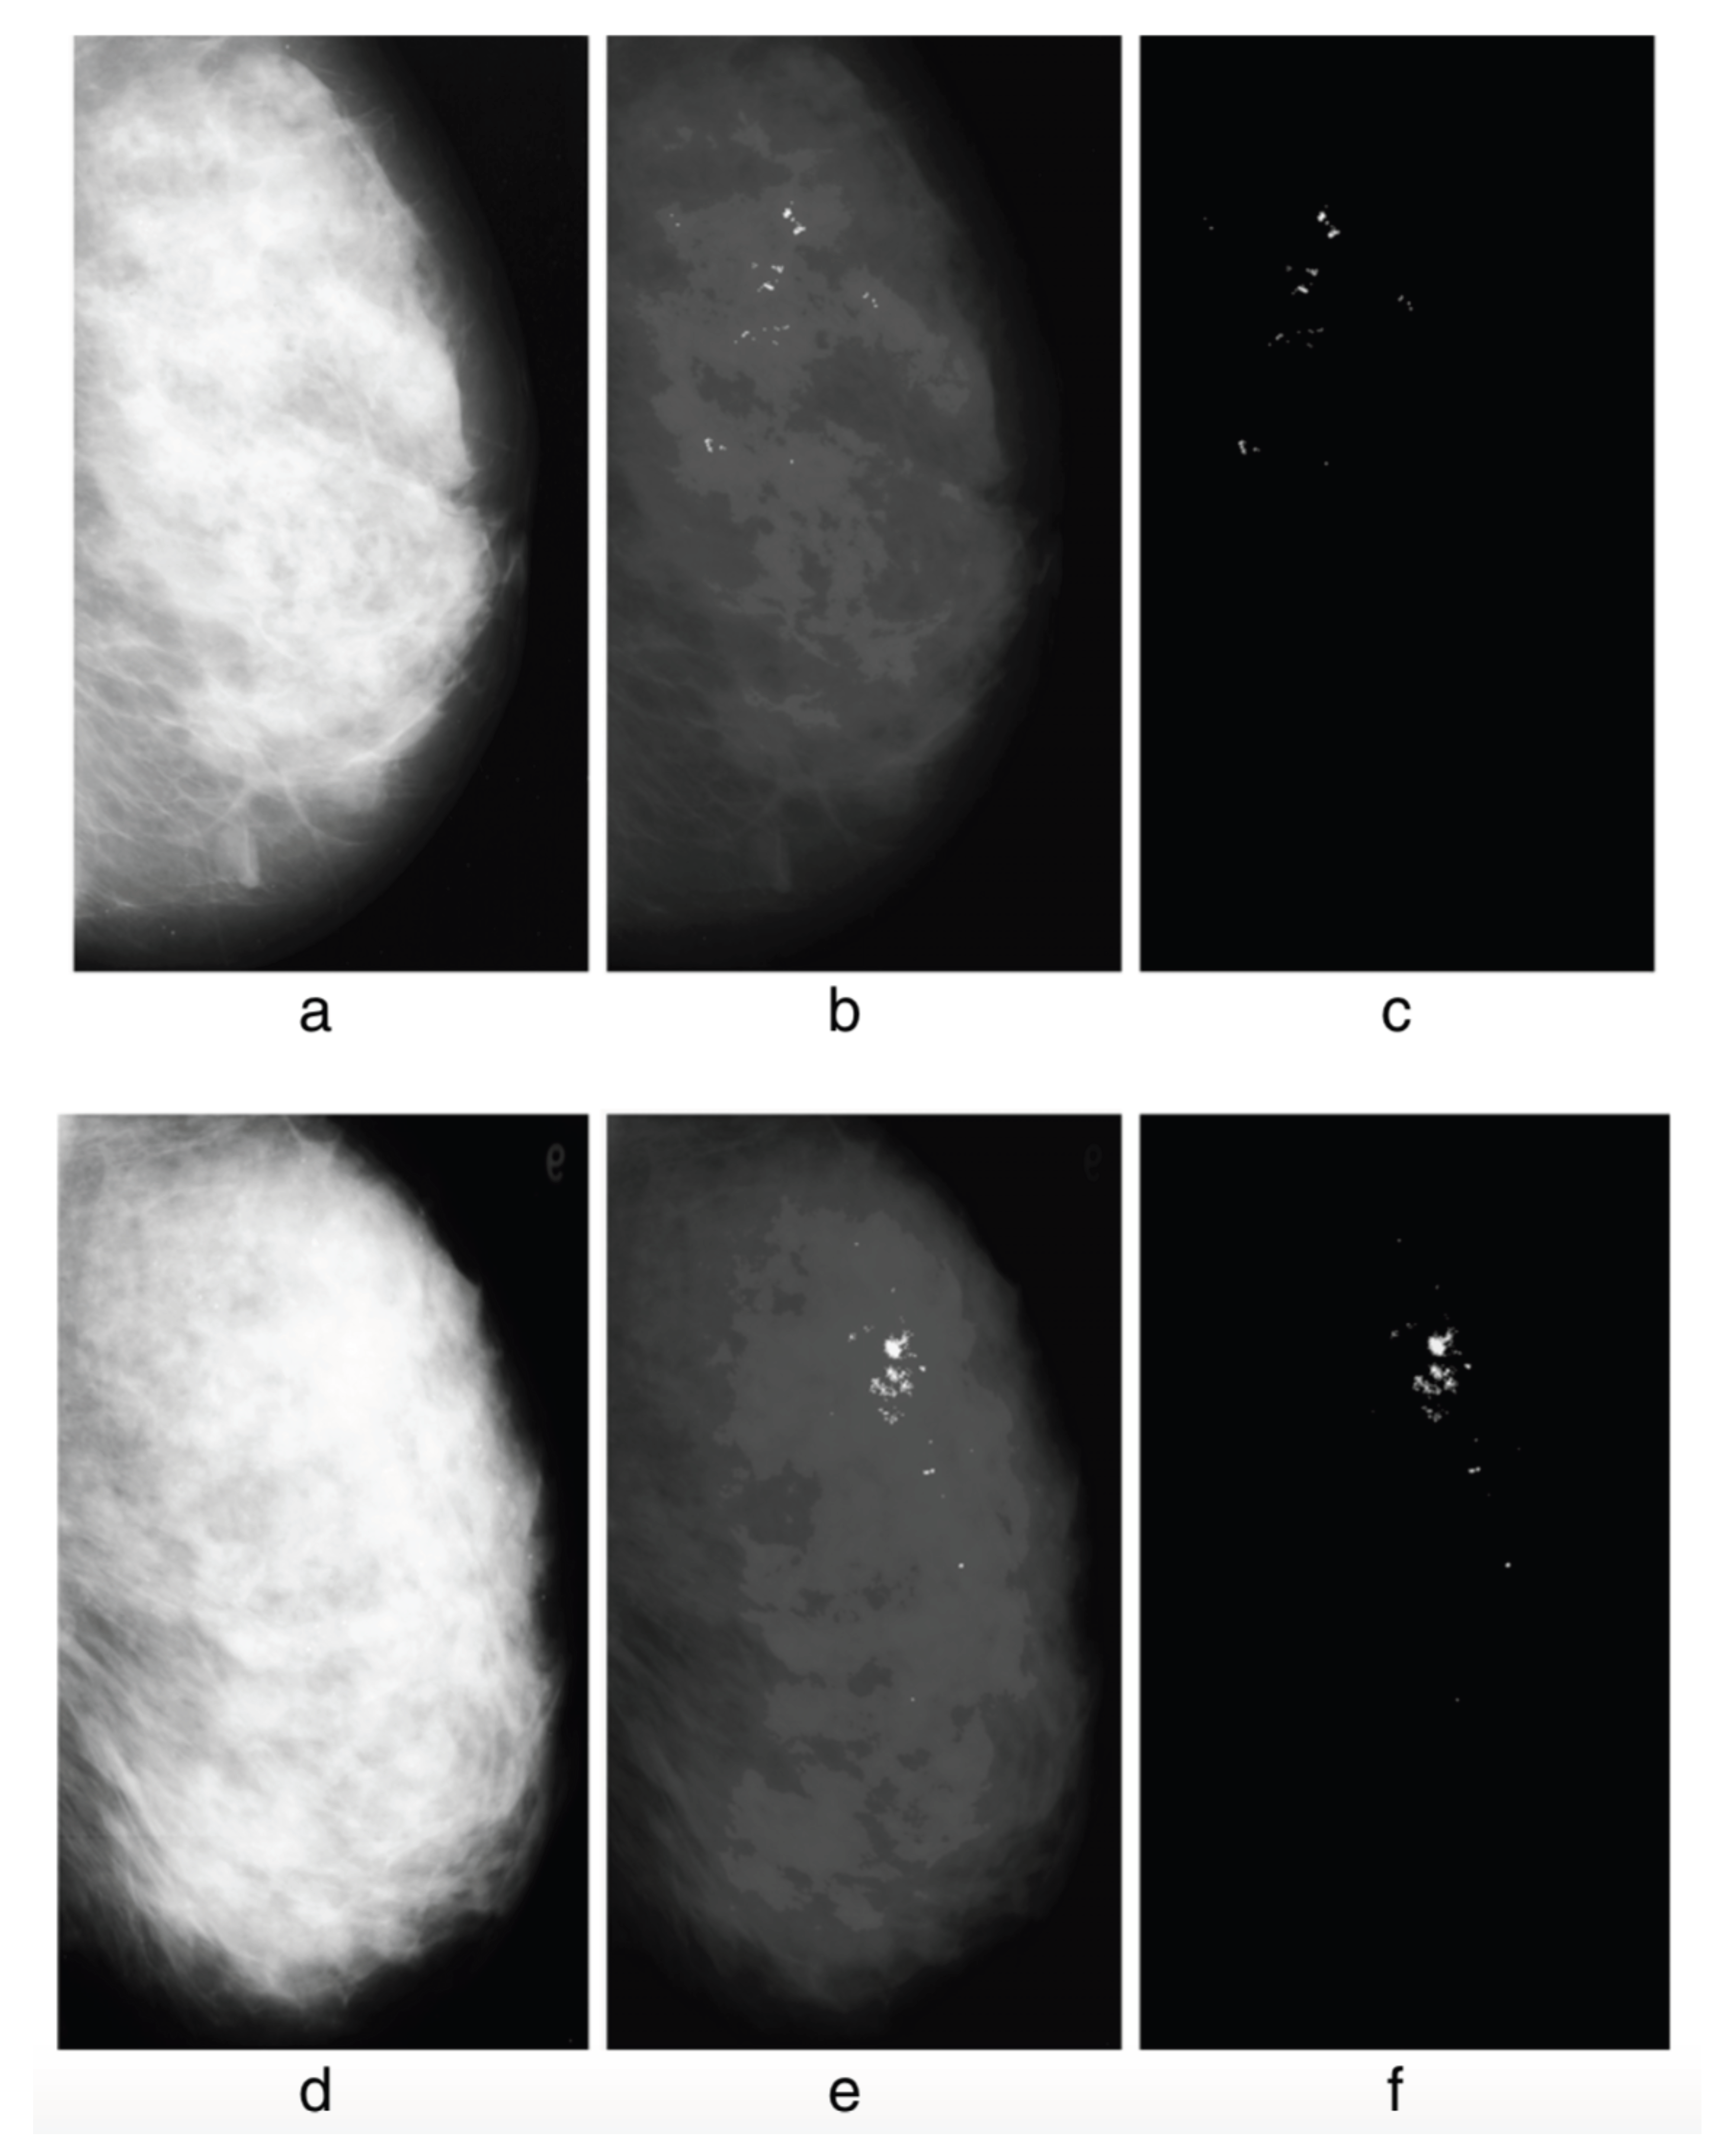

The detection of possibly pathological microcalcifications as revealed in mammograms can be sensibly improved by using q-entropy with [137], see Figure 26.

Figure 26.

Without q-entropy enhancement with , detection of microcalcifications is meager: 80.21% Tps (true positives) with 8.1 Fps (false positives), whereas upon introduction of the q-entropy, the results surge to 96.55% Tps with 0.4 Fps. Detection results from the experiment: (a) mdb236, (b) output with the Mcs enhanced, (c) output with the Mcs extracted, (d) mdb216, (e) output with the Mcs enhanced, (f) output with the Mcs extracted. From [137].